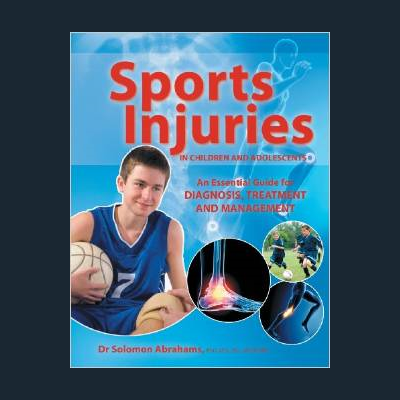

Solomon is one of a few UK Physiotherapists with a PhD Doctorate and has published a number of clinical articles on Musculoskeletal and Orthopaedic Medicine in scientific journals. He has also published two clinical text books, one of which is a best seller in the US. One book is dedicated to Children & Adolescent Sports Injuries and the other book is on Adult Sport Injuries.

His recent book, Sports Injuries in Children and Adolescents, has been well recieved and is selling well in globally, espceially the US. It is available from Amazon.